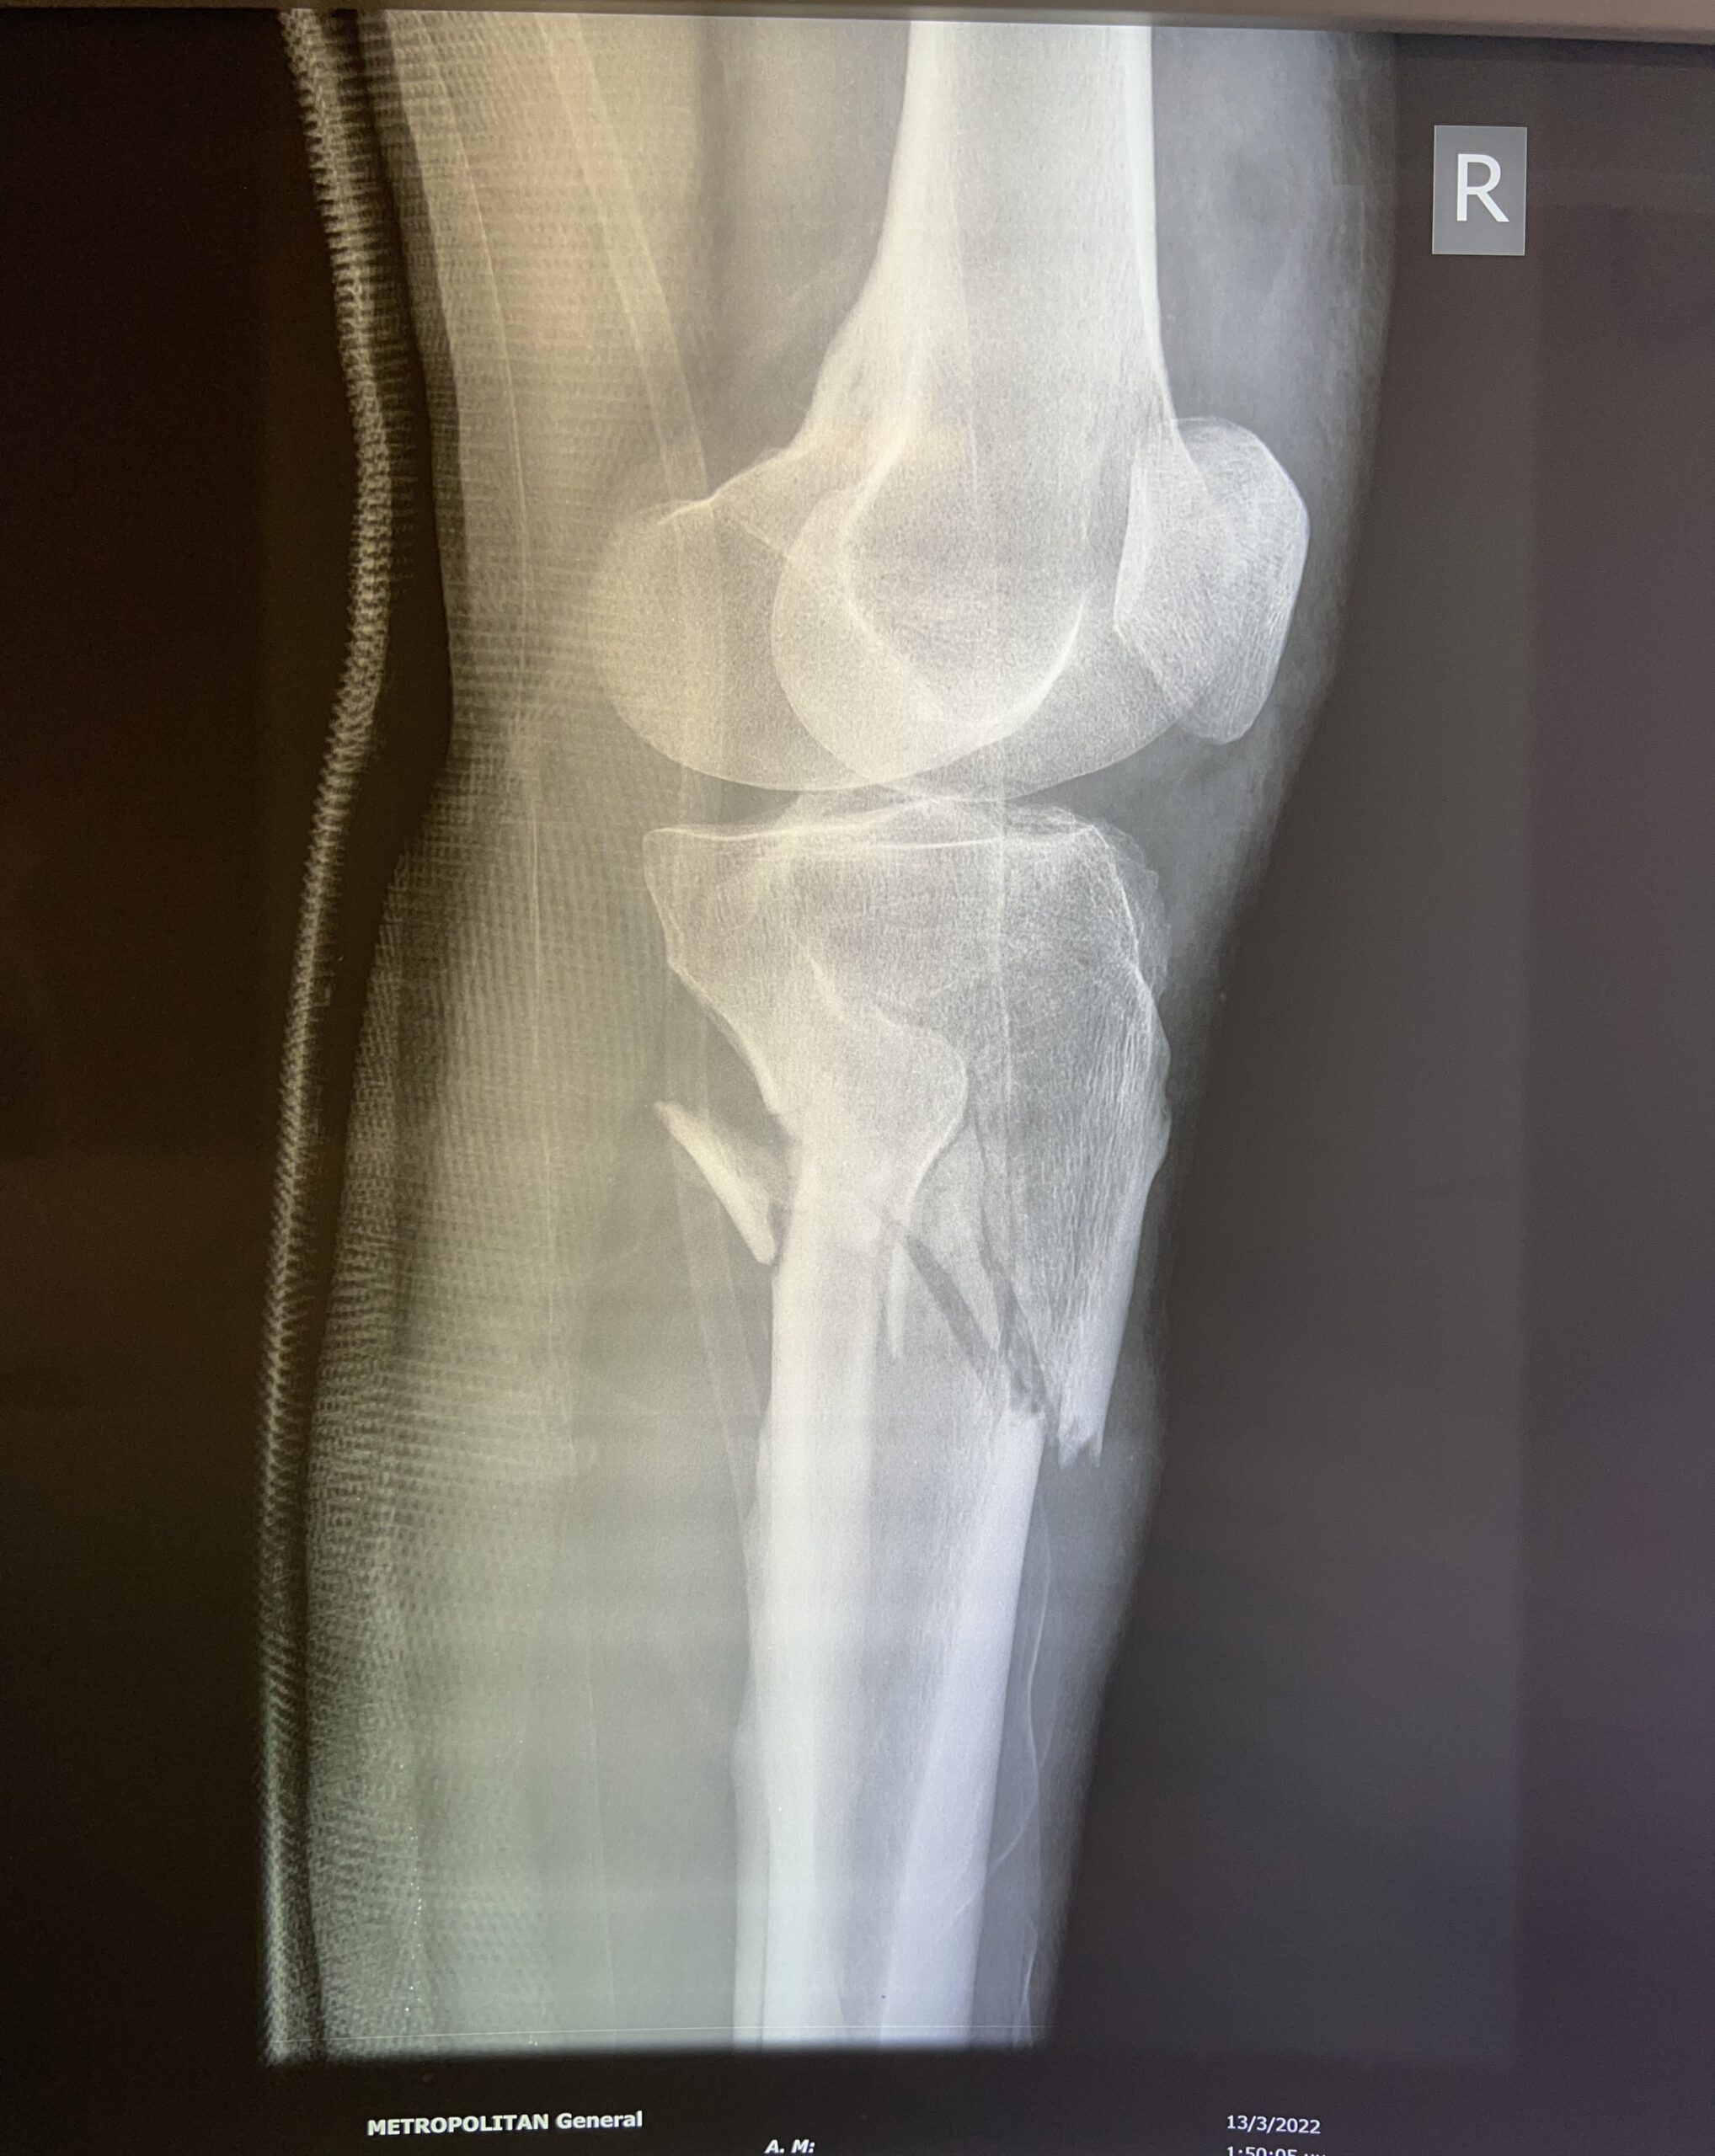

Η διάγνωση ενός κατάγματος κνημιαίου plateau πραγματοποιείται από έναν έμπειρο Ορθοπαιδικό. Αρχικά η λήψη ενός λεπτομερούς ιστορικού και η κλινική εξέταση του ασθενούς είναι απαραίτητα. Στην συνέχεια για την διάγνωση αλλά και την ταξινόμηση του κατάγματος είναι υποχρεωτική η διενέργεια ακτινολογικού ελέγχου. Ο έλεγχος αυτός περιλαμβάνει απλές ακτινογραφίες (φας, προφιλ και λοξές) ενώ πολλές φορές απαιτείται περαιτέρω διερεύνηση με αξονική τομογραφία για την πλήρη κατανόηση της μορφής του κατάγματος και τον σωστό προεγχειρητικό σχεδιασμό.

Ένα κάταγμα κνημιαίου plateau ανάλογα με τη σοβαρότητά του μπορεί να αντιμετωπιστεί είτε συντηρητικά είτε με χειρουργική επέμβαση. Σε κάθε περίπτωση τα κατάγματα κνημιαίου plateau θα πρέπει να αντιμετωπίζονται από εξειδικευμένους ορθοπαιδικούς, αποφεύγοντας έτσι κάποια μεταγενέστερη κινητική αναπηρία ή την εκδήλωση μετατραυματικής αρθρίτιδας.